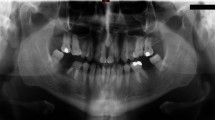

The provision of dental treatment under both local anaesthesia and sedation has an excellent safety record, although medical problems may occur. The high prevalence of cardiac disease in the population, particularly ischaemic heart disease, makes it the most common medical problem encountered in dental practice. Additionally, the increasing survival of children with congenital heart disease makes them a significant proportion of those attending for dental treatment. While most dental practitioners feel confident in performing cardio-pulmonary resuscitation, treating patients with co-existent cardio-vascular disease often causes concern over potential problems during treatment. This article aims to allay many of these fears by describing the commoner cardiac conditions and how they may affect dental treatment. It outlines prophylactic and remediable measures that may be taken to enable safe delivery of dental care.